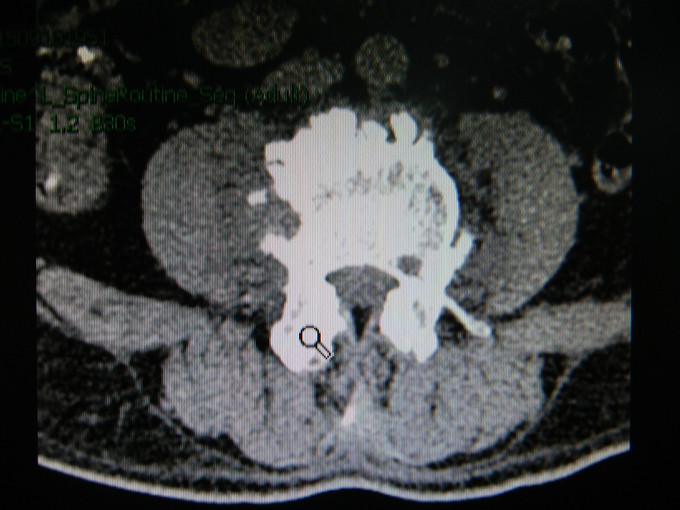

患者男,56岁。因“发热伴腰部疼痛3月”入院。现病史:患者于2015年6月中旬无明显诱因出现发热,体温多波动在37-38度之间,最高38.5摄氏度,下午为主,伴下肢关节疼痛。无鼻塞、流涕、喷嚏、咳嗽、咳痰、头痛、头晕、腹痛、腹泻等,以感冒给予治疗后症状无好转,7月中旬到当地医院就诊,考虑为布鲁氏菌感染,给予利福平4片/次,1次/日,多西环素1片/次,2次/日及相关治疗,症状无明显好转,后就诊我院,予以抗感染、退热及对症支持等治疗,确诊为“腰椎结核”后出院行抗结核治疗半月,门诊以“腰椎脓肿”收入我科。起病以来患者一般情况良好。

查体:生命体征平稳,心肺腹体检未见明显异常。专科情况无特殊。 辅助检查:MRI示腰椎椎体边缘骨质浓密、增生,部分骨赘骨桥形成。L2-5椎体及椎旁见不规则软组织密度影,与双侧腰大肌分界不清,结合病史符合感染性病变,结核可能性大;

诊断:腰椎结核。 治疗:全麻下行腰椎结核病灶清除术+内固定术。